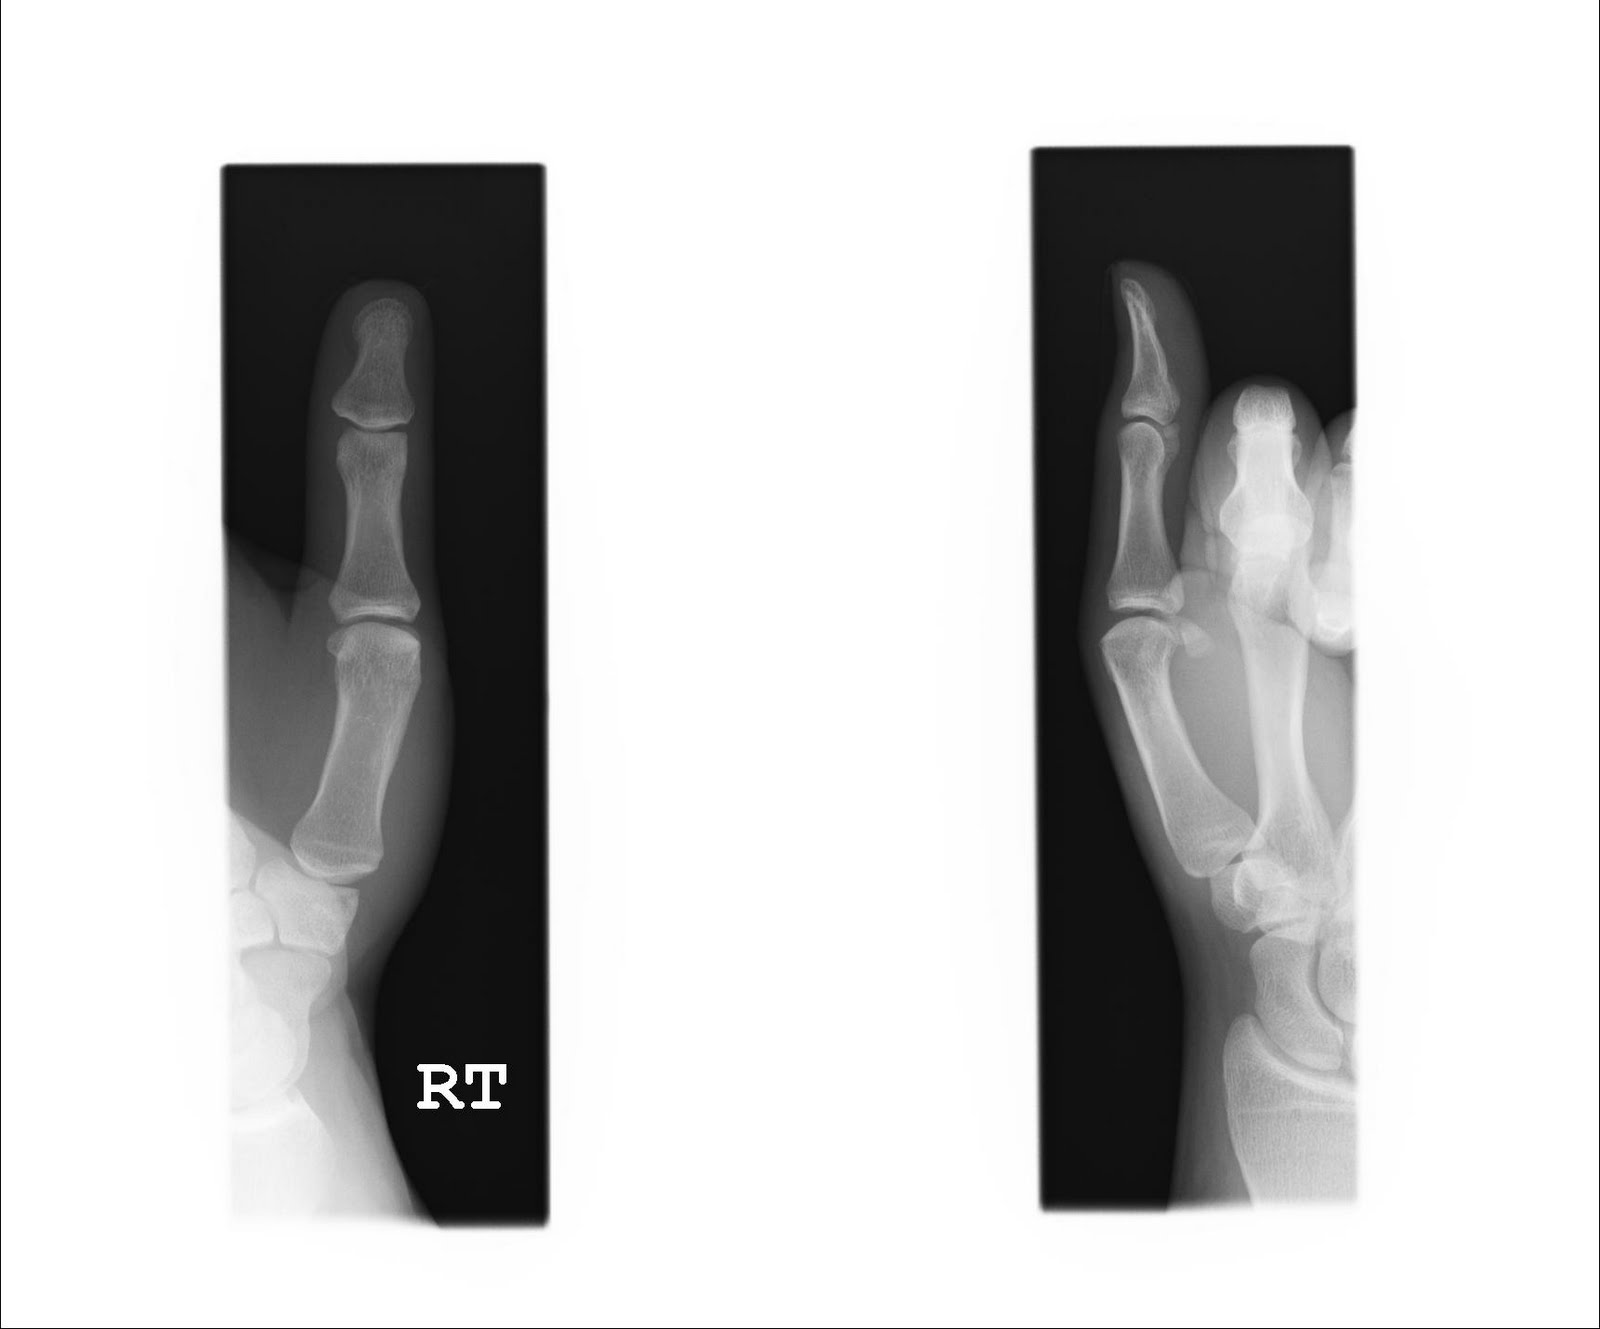

Oh yeah, I almost forgot. My thumb is getting better, although I cannot bend it yet. My ankle seems to be doing fine as well. My next appointment is the first week of November just four weeks away.